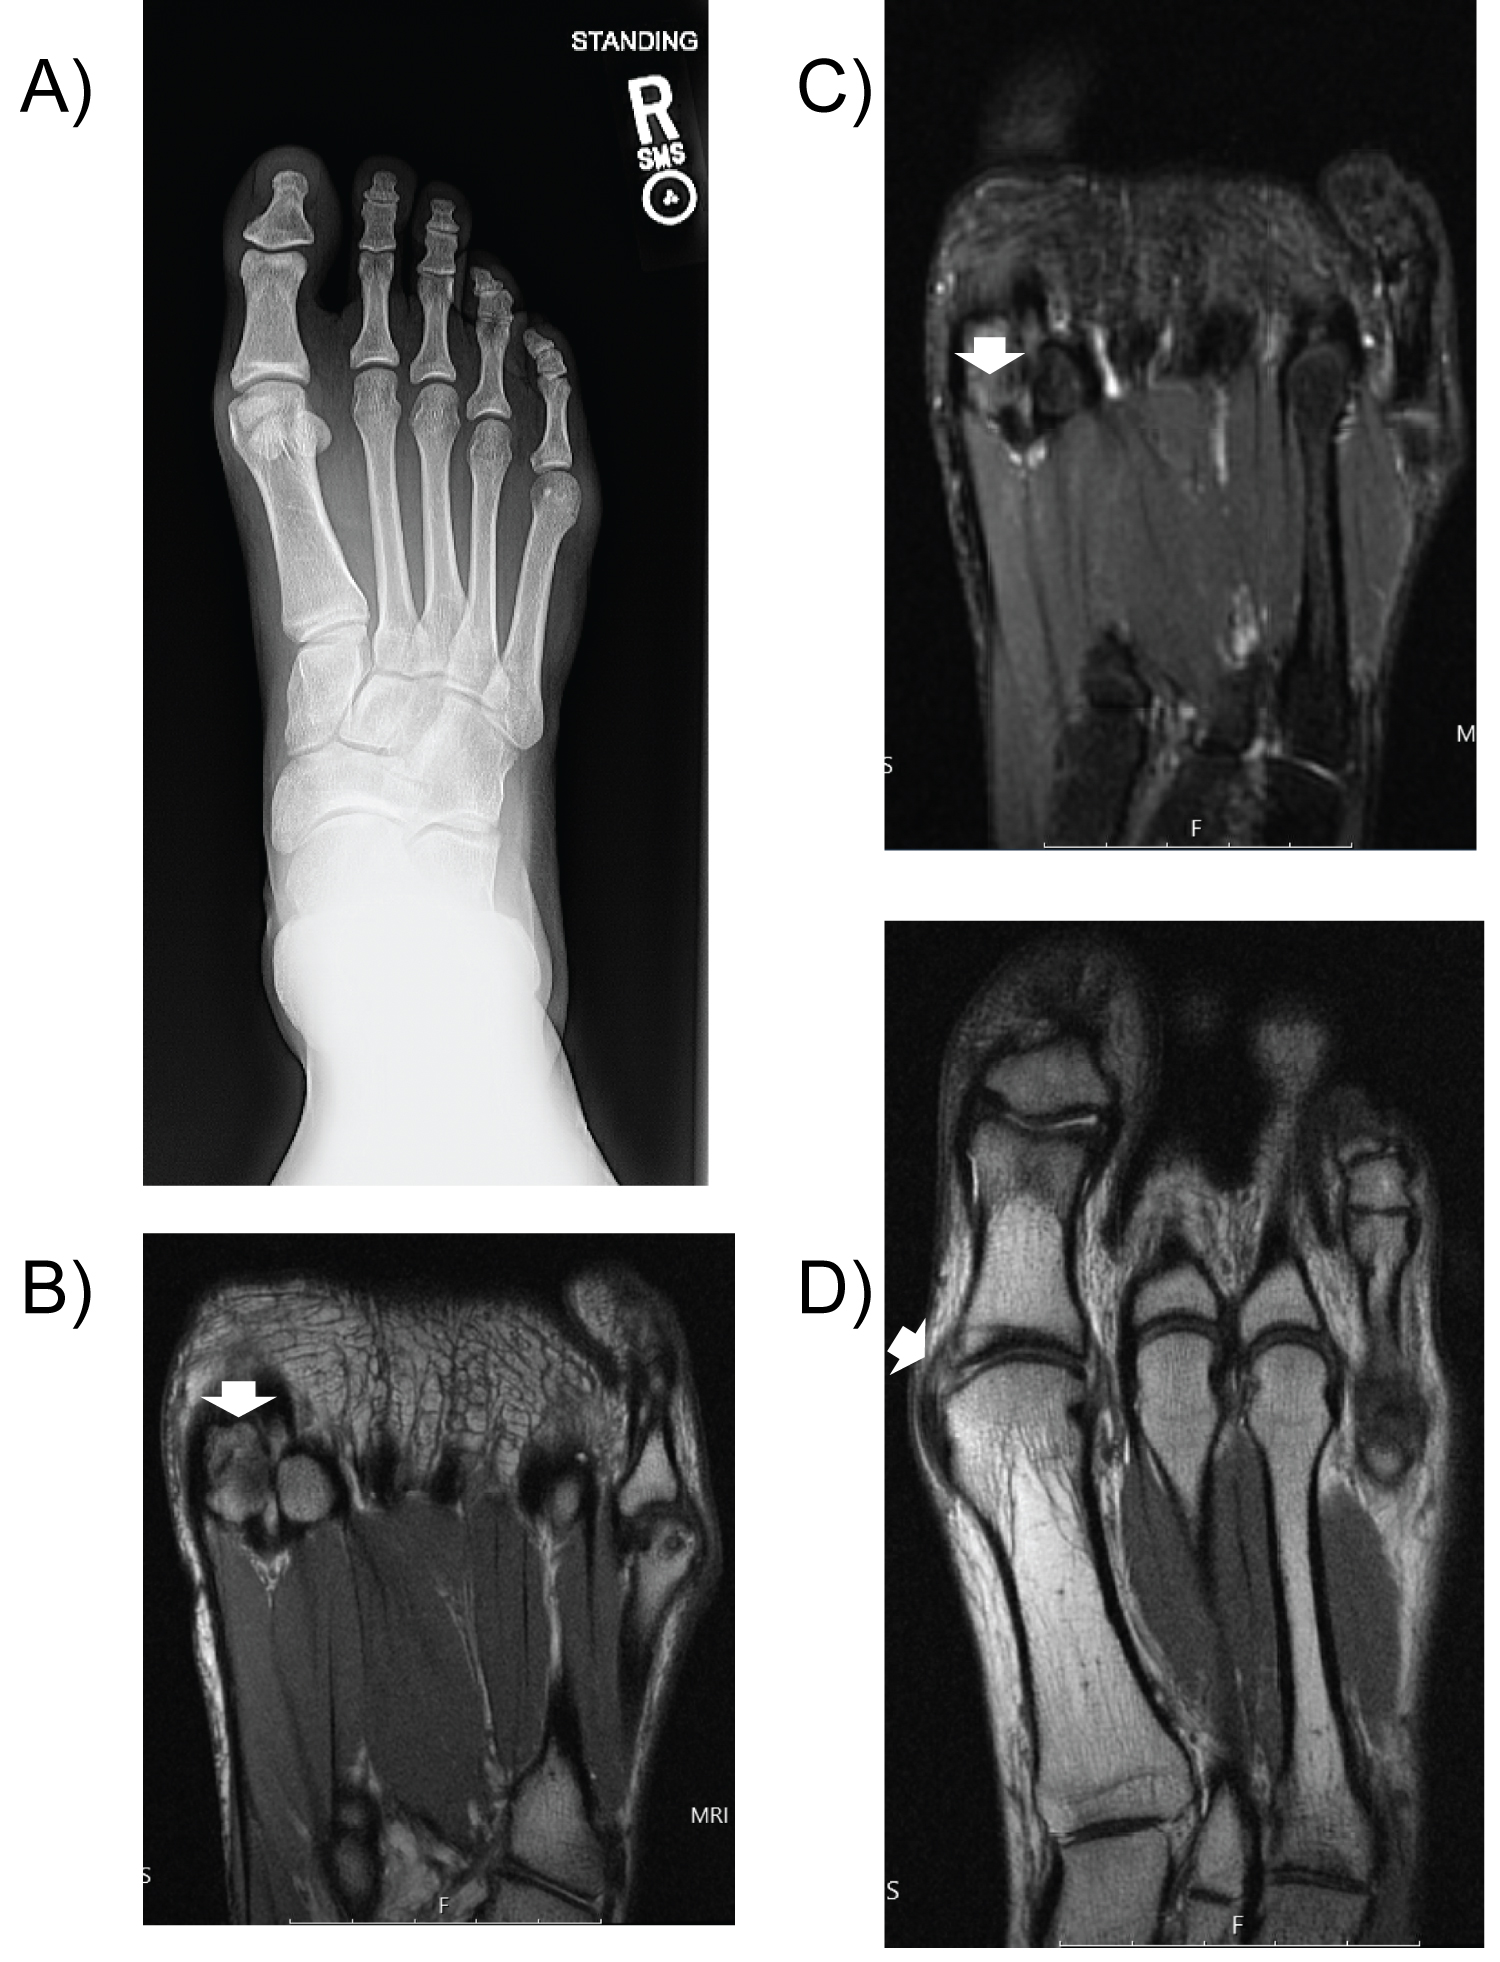

A 20-year-old male runner presented with first MTP joint pain after running nine weeks prior. The pain was 7/10, exacerbated by standing and running. Pain persisted despite rest, heat/ice, NSAIDs, and immobilization in a boot for 2-3 weeks before transitioning to rocker-bottom running shoes. Exam demonstrated tenderness at the sesamoids and flexor hallucis brevis (FHB), full and painless ROM, and full strength. X-rays showed lateral sesamoid deformity. MRI revealed incomplete fracture of the lateral sesamoid and associated synovitis (Figure 4).

Figure 4: Case Two. a) X-rays of the right foot (sesamoid view) demonstrates cortical irregularity at lateral sesamoid (arrow). MRI of right forefoot (proton density sequence) demonstrates cortical irregularity in lateral sesamoid suspicious for nondisplaced incomplete fracture as seen on coronal (b) and axial (c) views (arrows). D) MRI of right foot (inversion recovery sequence) demonstrates trace edema within the sesamoid (arrow). View Figure 4

Six weeks after PRP injection, he had completed PT with consistent HEP. He reported 80% improvement in pain. At one year follow up, he endorsed 100% improvement and returned to hiking and running without pain or functional limitations.